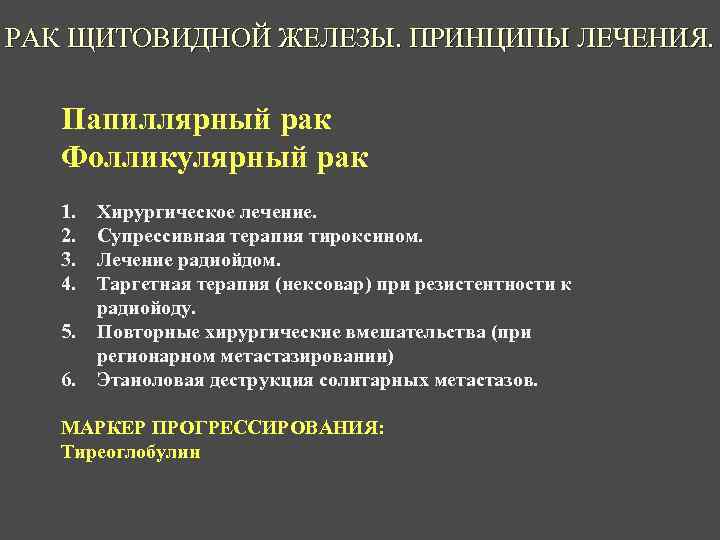

РАК ЩИТОВИДНОЙ ЖЕЛЕЗЫ. ПРИНЦИПЫ ЛЕЧЕНИЯ. Папиллярный рак Фолликулярный рак 1. 2. 3. 4. 5. 6. Хирургическое лечение. Супрессивная терапия тироксином. Лечение радиойдом. Таргетная терапия (нексовар) при резистентности к радиойоду. Повторные хирургические вмешательства (при регионарном метастазировании) Этаноловая деструкция солитарных метастазов. МАРКЕР ПРОГРЕССИРОВАНИЯ: Тиреоглобулин